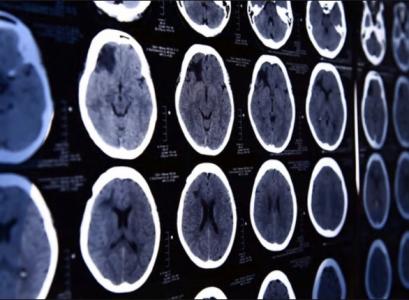

L'insuffisance vasculaire cérébrale définie comme un flux sanguin insuffisant vers le cerveau augmente le risque d'accident vasculaire cérébral et est une cause majeure de décès et d'invalidité neurologiques. Elle est généralement causée par l'athérosclérose ou l’accumulation de graisses, de cholestérol et d'autres substances qui obstruent les artères qui irriguent le cerveau.

Ces dernières décennies, les techniques permettant de restaurer le flux sanguin dans les zones du cerveau compromises, touchées ou menacées par l’AVC ou encore les artères obstruées, ont connu "une explosion spectaculaire", souligne ce rapport de neurologues et de neurochirurgiens de la Loyola Medicine. Un constat à paraître dans la revue MedLink Neurology qui rend hommage aux progrès en thrombectomie mécanique et des techniques mini-invasives.